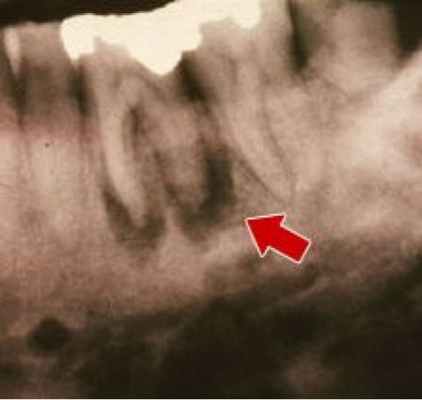

Складывается из клинической картины и рентгенологических признаков. На рентгенограмме к концу 3-й и на 4-й неделе можно заметить остео-пороз кости в области гнойного очага, небольшие участки деструкции. На более поздних снимках можно увидеть изменения, происходящие в области свободно лежащих омертвевших костных осколков и живых костных участков, не потерявших всязи с мягкими тканями.

Если лечение не начато или прошло неудачно, то остеомиелит челюсти переходит в хронический. Самочувствие пациента нормализуется, температура может быть нормальной или время от времени немного повышаться. Из-за утолщения челюсти и изменений слизистой и кожи изменяется лицо в месте поражения: мышцы становятся очень плотными («желваки»), тонкая сухая кожа над ними натянута, рот немного перекошен. Зубы в области остеомиелита расшатываются, выпадают. На месте свищей появляются рубцы. В кости начинается процесс секвестрации: из-за некроза от кости отламываются фрагменты. Секвестрирующий остеомиелит верхней челюсти развивается быстро, в течение 4-6 недель, а нижней — до 14 недель и дольше. Эти кусочки кости распадаются или выходят через свищи с гноем. Их хорошо видно при рентгеновской диагностике остеомиелита челюстей: истончённая пористая кость челюсти, рядом секвестры (отломки). При длительном процессе развивается остеосклероз — болезненное утолщение кости с утратой её упругости [1, 2] .

При запущенной форме заболевания (хроническая или подострая стадия) изменения костной ткани уже значительны и заметны, поэтому рекомендуется рентген или компьютерная томография челюсти. Такие методы помогают увидеть образовавшиеся участки омертвевшей ткани (секвестры), а также понять насколько глубоко распространился воспалительный процесс.

- Сделать рентгеновский снимок. При острой форме он малоинформативен, но при подострой и хронической патологии будут заметны участки изменения плотности кости и участки отмершей костной ткани.

Выводы врача требуют рентгенографического подтверждения. На снимке будет видно местоположение очага остеомиелита, участков деструкции и уплотнения кости, некротических фрагментов и омертвевших зачатков зубов. Однако в сложных случаях остеомиелита кости обычного рентгена может быть недостаточно и пациента направят на томографию. Кроме того, при наличии свищей может потребоваться фистулография, в процессе которой в каналы с гнойным отделяемым вводят специальное вещество, а затем проводят их рентгеноскопию.